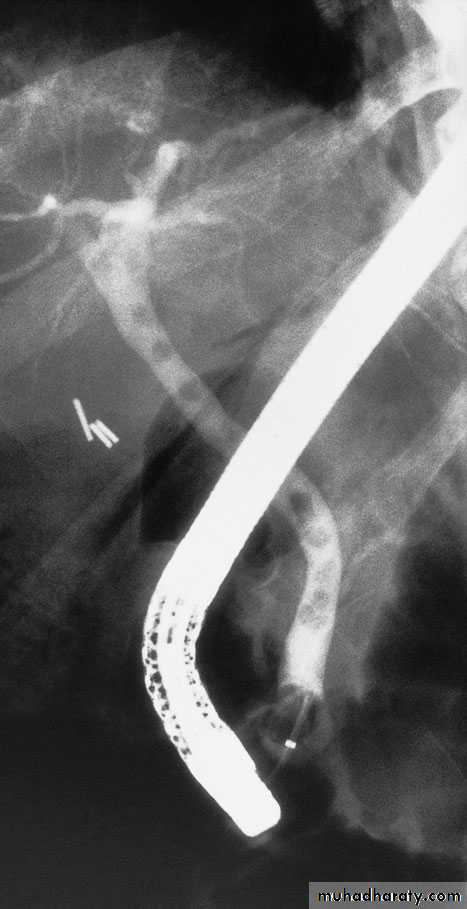

Endoscopic retrogradecholangiopancreatographyThis technique remains widely used. Using a side-viewing endoscope,the ampulla of Vater can be identified and cannulated.Injection of water-soluble contrast directly into the bile ductprovides excellent images of the ductal anatomy andcan identify causes of obstruction such as stones ormalignant strictures , Bile can be sent for cytological and microbiological examination, and brushings can be taken from strictures for cytological studies. Therapeutic interventions such as stone removal or stent placement to relieve the obstructioncan be performed. Thus, ERCP has evolved into a mainly therapeutic rather than a diagnostic uses .

Percutaneous transhepatic cholangiographyThis is an invasive technique in which the bile ducts are cannulated directly. It is only done once a bleeding tendency has been excluded, Antibiotics should be given prior to the procedure. Usually,, a needle is introduced percutaneously into the liver substance. Under radiological control (either ultrasound or CT), a bile duct is cannulated. Successful entry is confirmed by aspiration of bile. Water-soluble contrast medium is injected to demonstrate the biliary system. In addition, PTC enables the placement of a catheter into the bile ducts to provide external biliary drainage or the insertion of stents.